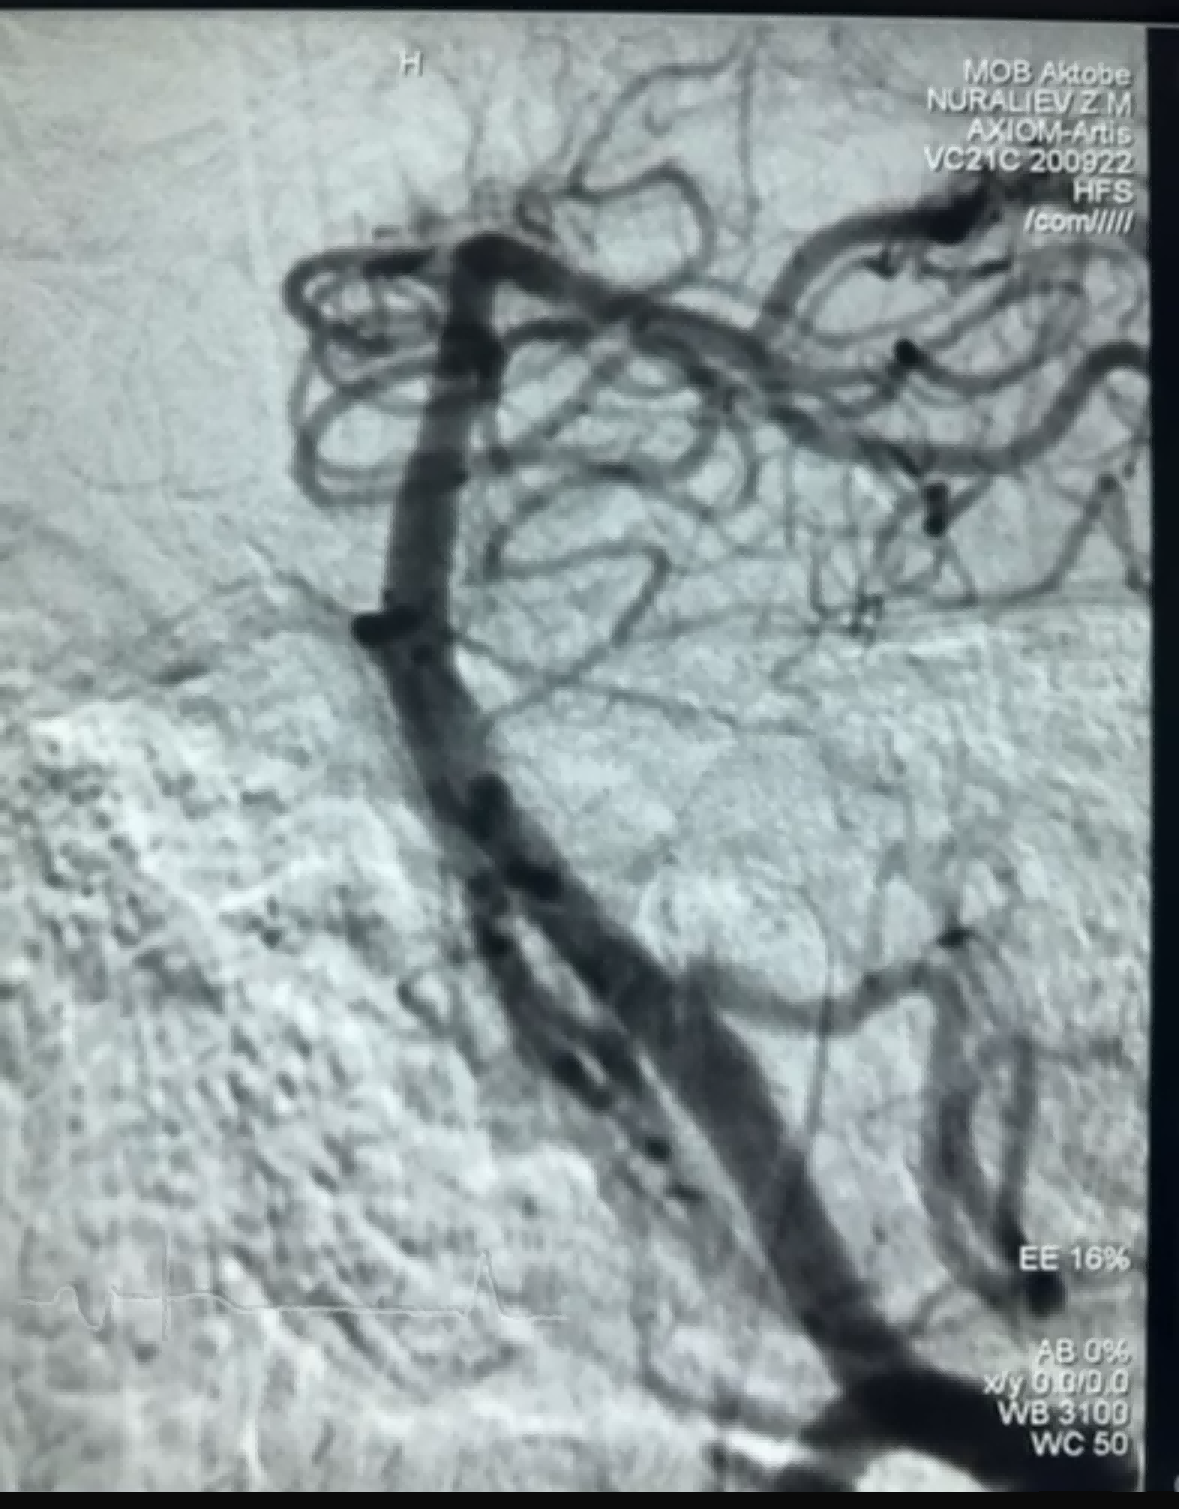

Gần đây, đã có một ca lấy huyết khối thành công khi sử dụng Dredger Stent Retriever của Công ty TNHH NeuroSafe Medical. Dredger Stent Retriever có đầu mềm không xâm lấn, giúp giảm đáng kể nguy cơ tổn thương nội mạc và có thiết kế lỗ hình dạng đặc biệt độc đáo, chủ yếu giữ lại các cục máu đông bằng cách kẹp chặt các khoảng trống thay đổi.